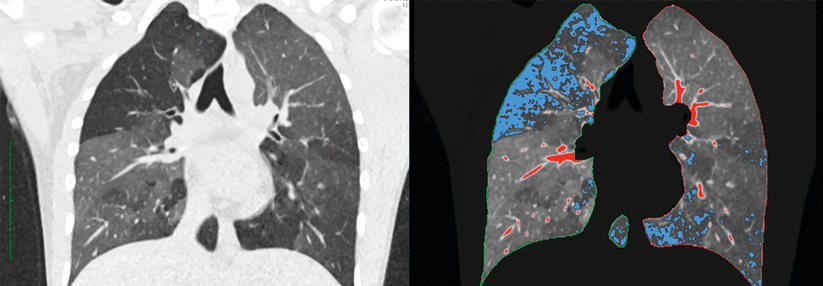

Beim metastasierten NSCLC sind Immuncheckpoint-Inhibitoren mit oder ohne Chemotherapie mittlerweile Standard, wie es auf der ESMO-Jahrestagung bestätigt wurde. Beim metastasierten NSCLC sind Immuncheckpoint-Inhibitoren mit oder ohne Chemotherapie mittlerweile Standard, wie es auf der ESMO-Jahrestagung bestätigt wurde. © WindyNight – stock.adobe.com

Immuncheckpoint-Inhibitoren mit oder ohne Chemotherapie sind mittlerweile Standard in der Erstlinienbehandlung des metastasierten NSCLC, das keine therapeutisch adressierbaren Treibermutationen aufweist. Auf der ESMO-Jahrestagung wurden 5-Jahres-Daten vorgestellt, die den Standard bestätigen. Neue Ergebnisse gab es auch zur Kombination aus Durvalumab und Tremelimumab.